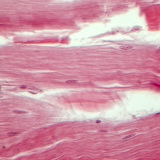

Шөрмөс (уртааш огтлол)

400 дахин томруулсан